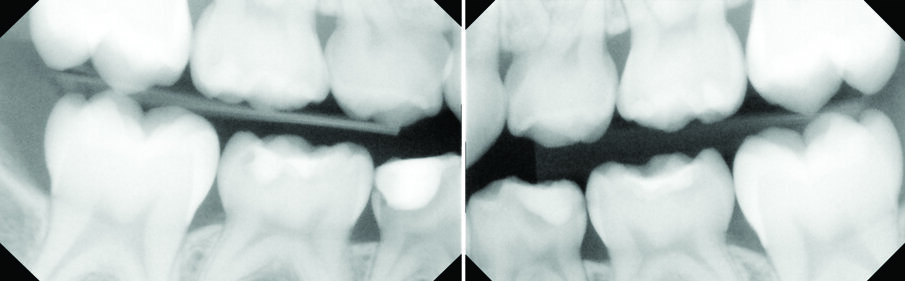

Figs. 4 (a & b). Patient LT, who was dentally anxious, also had dental caries which the above bitewings show.

An eight and half year-old girl (LT) attended the paediatric dentistry department of Hamdan Bin Mohammed College of Dental Medicine (HBMCDM) in Dubai Healthcare City for an opinion. The patient’s mother was concerned about the delayed eruption of an upper front tooth (21) that was affecting her child’s appearance (Figs. 1 a, b & c). LT was medically fit and healthy with no history of previous dental trauma. She was in the mixed dentition stage. Tooth 11 had erupted 4 months ago in cross bite but 21 had not erupted yet. Its eruption was much delayed (usually erupts at 7 ½ years of age). Looking back at previous x-rays, a DPT was taken a year ago and it was noticed that an important feature was missed. Retrospectively, the presence of a supernumerary tooth ($) in the area of 21 and congenital missing 47 was confirmed (Fig. 2). Two new x-rays, namely upper intra oral periapicals and the parallax technique (distal shift) showed a supernumerary tooth (conical and inverted) in a palatal position (Figs. 3 a & b). LT also had dental caries of her primary teeth (Figs. 4 a & b), had a pronounced gag reflex and was dentally anxious.